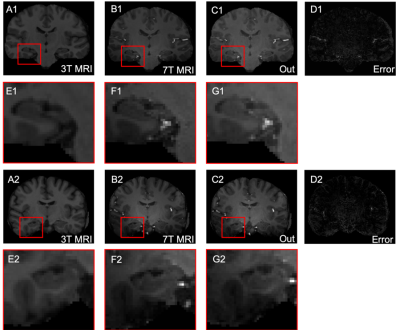

Figure 1: Results of 7T MRI reconstruction using FocalGAN on two testing pairs shown in coronal view. 3T MRI (A) is the input, 7T MRI (B) is the reference, Out (C) designates the reconstruction generated by FocalGAN, error maps (D) are shown in the right-most column. Regions outlined in red are expanded beneath the relevant panel (E-G).